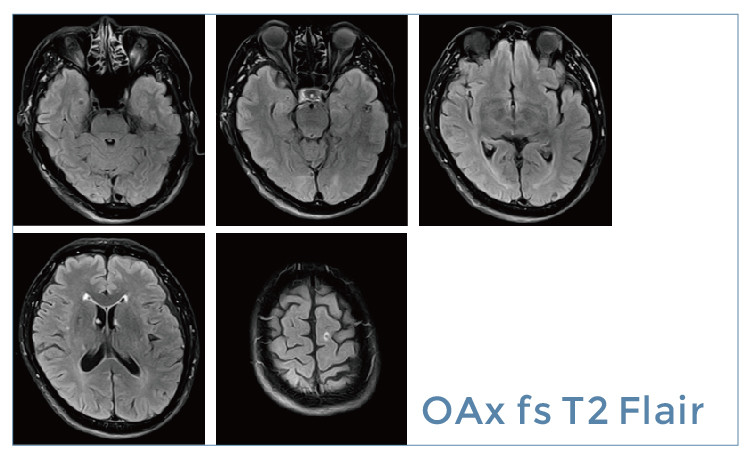

【朗润影像档案】磁共振影像病例分享(编号20190524)